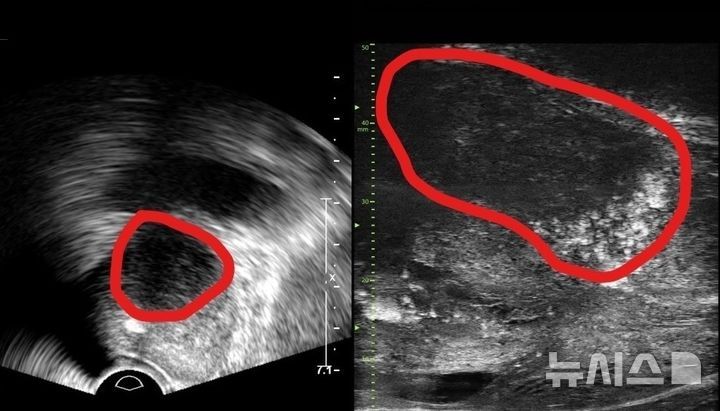

분당서울대병원 비뇨의학과는 기존 경직장 초음파보다 해상도가 약 3배 높은 실시간 영상을 제공하는 29메가헤르츠 마이크로 초음파 장비를 국내 최초로 도입했다고 24일 밝혔다. 이 장비는 전립선과 주변 해부학적 구조를 고해상도로 표시해 종양 의심 부위를 세밀하게 평가하고, 해당 부위를 직접 겨냥하는 표적 조직검사를 유도한다.

분당서울대병원 측은 장비가 실시간 영상과 표적 바늘 유도 기능을 결합해, 암 의심 부위에 조직검사 침을 정확히 삽입하도록 돕는 점을 차별점으로 꼽는다. 기존 경직장 초음파는 해상도가 낮아 종양 경계를 명확히 구분하기 어렵고, 작은 병변은 아예 보이지 않는 경우도 적지 않았다. 이 때문에 일정 간격으로 여러 부위를 광범위하게 찌르는 체계적 생검 방식이 일반적이었고, 환자 부담과 합병증 위험이 뒤따랐다.

마이크로 초음파는 영상에서 보이는 의심 병변을 직접 겨냥하는 표적 생검 접근을 강화한다. 고해상도 덕분에 주변 정상 조직과 병변의 질감과 에코 패턴 차이를 더 뚜렷하게 구분할 수 있어, 병변 경계를 따라 침을 넣거나 병변 중심부를 정확히 채취하는 전략적 샘플링이 가능해진다.

마이크로 초음파의 등장은 MRI 중심으로 굳어진 전립선암 영상 진단 체계에도 변화를 예고한다. 현재 고위험 전립선암 진단에는 자기공명영상과 초음파 융합 표적 생검이 널리 사용되지만, MRI에서 병변을 찾지 못하는 경우도 존재한다. 특히 아주 작은 크기의 미세암이나 경계가 모호한 병변은 MRI 해상도와 판독자의 경험에 따라 놓칠 수 있는 한계가 지적돼 왔다.